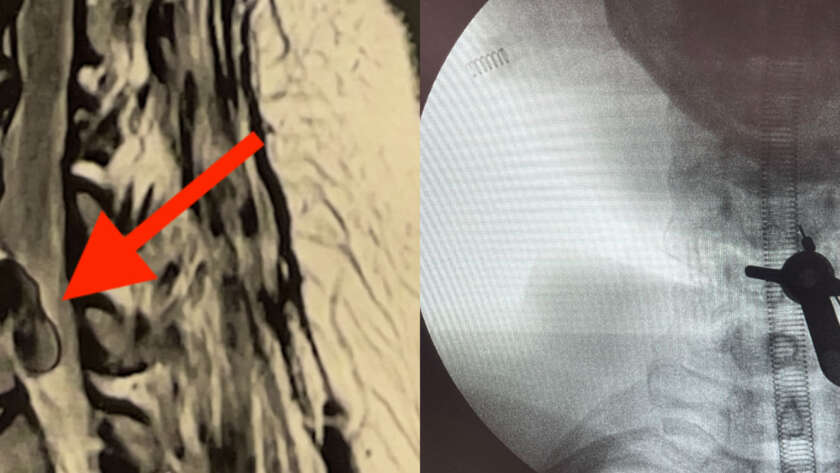

Paciente do sexo masculino, 34 anos, atleta, procurou atendimento com quadro de dor cervical de início agudo, associada à irradiação para o membro superior esquerdo, com impacto direto em suas atividades esportivas e rotina diária.

Inicialmente, foi instituído tratamento conservador, incluindo uso de medicações analgésicas e anti-inflamatórias, associado à reabilitação fisioterapêutica. Apesar da adequada adesão…